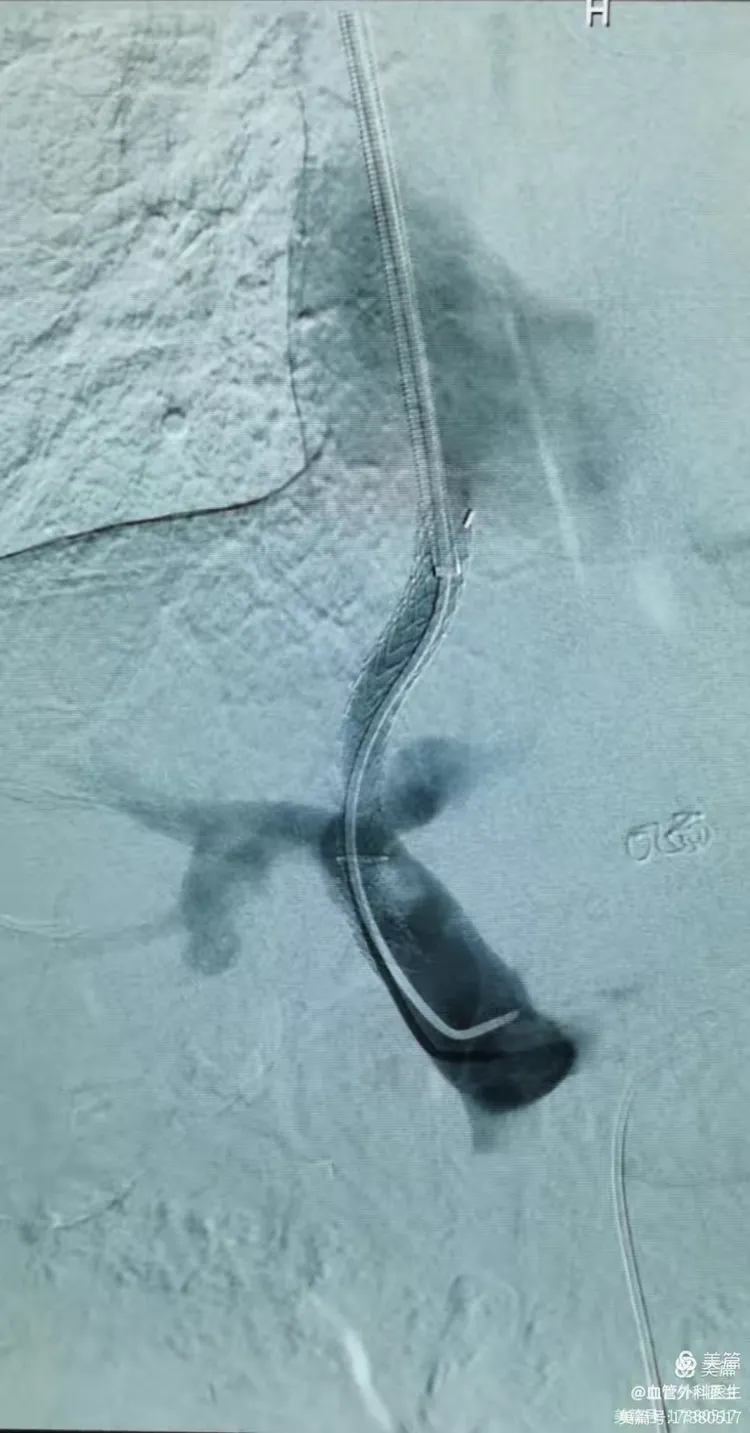

门脉高压断流手术利弊

1、1分流术可直接将门静脉压力降低,但分流后由门静脉流入肝脏的血液减少,因此胃肠道吸收的营养物质通过肝脏分解代谢的量亦较少,影响人体营养物质的吸收2患者采取断流术治疗后,大量的血液仍由门静脉流入肝脏,人体吸收的营养物...